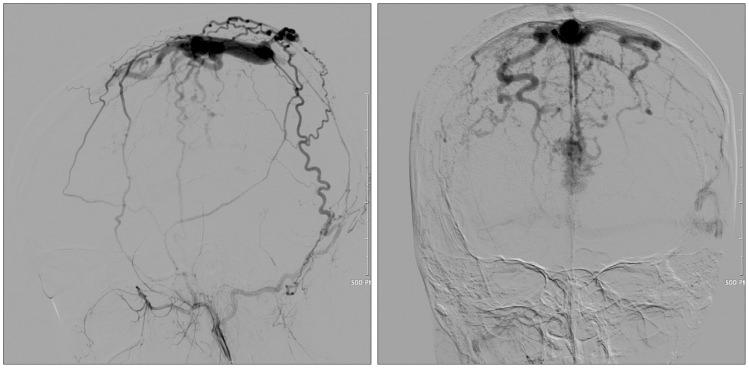

We are reporting an unusual case of dural arteriovenous fistula (AVF) of the superior sagittal sinus (SSS) after tamoxifen treatment for breast cancer. A 30-year-old female arrived at the emergency room with a sudden headache and left sided weakness and sensory loss. In her past medical history, she was diagnosed with breast cancer 1 year prior, and subsequently underwent a breast conserving mastectomy with whole breast radiation and adjuvant chemotherapy with tamoxifen. At the time of admission, computed tomography showed a small acute intracerebral hemorrhage at the right parietal cortex, and magnetic resonance imaging showed that a dural AVF at the SSS with a prominent and tortuous venous enhancement along the centrum semiovale was present. Cerebral angiography showed that the dural AVF at the mid-portion of the SSS with meningeal arterial feeding vessels entering the wall of the SSS, then draining through the dilated cortical veins. Our patient had no signs of active malignancy or any abnormalities in her coagulation profile, so it can be concluded that the tamoxifen was the likely cause of the SSS thrombosis and dural AVF. The dural AVF was treated by an endovascular coil embolization for the arterialized segment of the SSS. The patient dramatically recovered favorably from left side motor and sensory deficit. The best clinical approach is to screen potential patients of tamoxifen hormonal therapy and educate them on the sign and symptoms of life threatening thromboembolic events while taking tamoxifen.

我们报告了一例在他莫昔芬治疗乳腺癌后发生上矢状窦(SSS)硬脑膜动静脉瘘(AVF)的罕见病例。一名30岁女性因突发头痛、左侧肢体无力和感觉丧失入住急诊室。既往病史显示,她1年前被诊断为乳腺癌,随后接受了保乳乳房切除术、全乳放疗以及他莫昔芬辅助化疗。入院时,计算机断层扫描显示右侧顶叶皮质有一小片急性脑内出血,磁共振成像显示SSS处存在硬脑膜AVF,沿半卵圆中心有明显且迂曲的静脉强化。脑血管造影显示SSS中部的硬脑膜AVF,有脑膜动脉供血血管进入SSS壁,然后通过扩张的皮质静脉引流。我们的患者没有活动性恶性肿瘤迹象,凝血指标也无任何异常,因此可以得出结论,他莫昔芬可能是导致SSS血栓形成和硬脑膜AVF的原因。通过血管内弹簧圈栓塞术治疗了SSS动脉化段的硬脑膜AVF。患者左侧运动和感觉功能障碍显著好转。最佳临床处理方法是筛查他莫昔芬激素治疗的潜在患者,并告知他们在服用他莫昔芬期间危及生命的血栓栓塞事件的体征和症状。